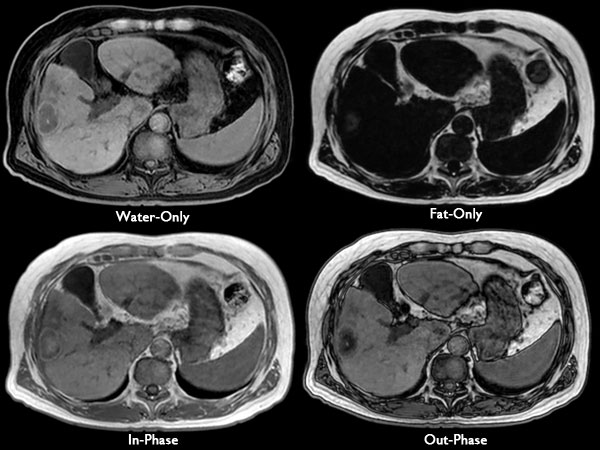

Axial mDIXON (high resolution)